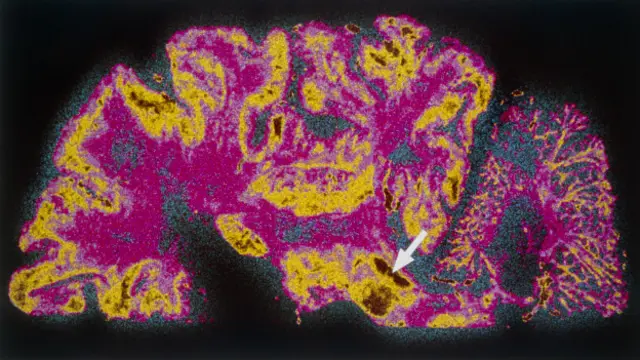

新加坡的科学家们说,他们已经创造出世界上第一个人造微型“中脑”,即人脑包括视力,听力和活动控制的部分。

这个创造出来的标本只有两毫米宽,是大脑的信息高速公路中脑的一个微缩版本。

科学家们说创造了带有神经黑色素的微缩中脑版本。

这种神经黑色素是正常大脑有的东西,但在帕金森氏病患者的脑中则消失了,人们不知道为什么会消失。